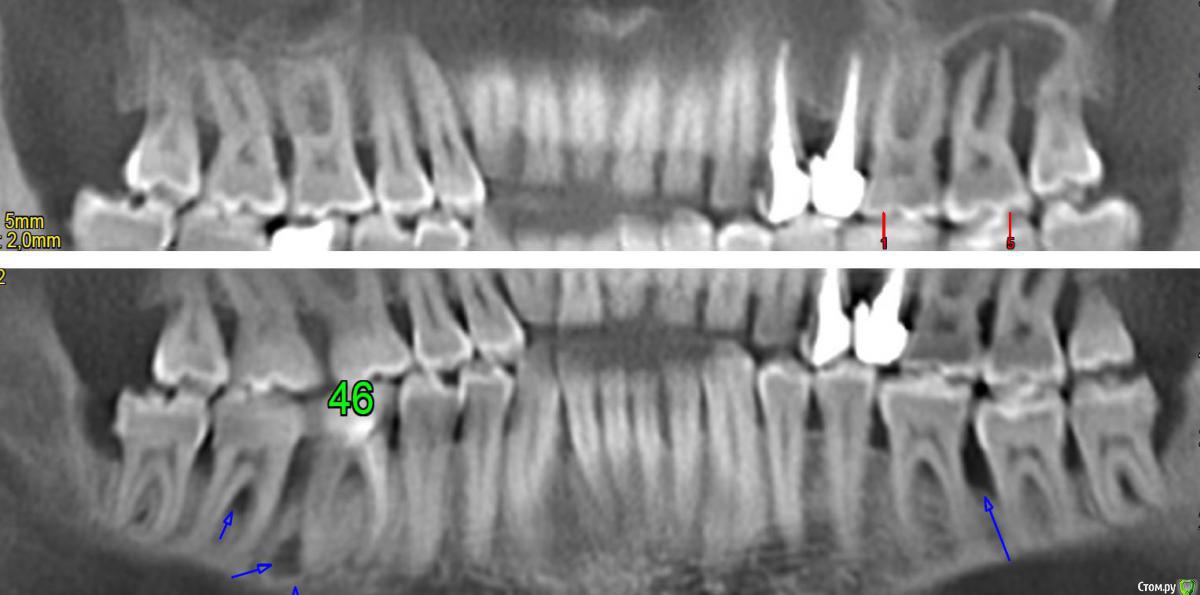

Макс111 Опубликовано 16 декабря, 2015 Поделиться Опубликовано 16 декабря, 2015 Добрый день!По возможности, прошу посмотреть мою КТ. Правда, не разобрался какую именно папку выкладывать, поэтомувот тут ссылка только на папку с файлами с расширением .DCM https://yadi.sk/d/NQrtBNRKmFtRC А вот тут на все содержимое диска вместе с программой для просмотра, на всякий случай:https://yadi.sk/d/O5yoL0QImFu3Y Так же к теме прикрепляю фото 24, 25 с внешней и внутренней стороны, а так же фото ниж ч там где 46 У меня пародонтит, и тд.В целом, вопрос по 24 и 25 зубу, между ними как видно большой карман. 25 это коронка на зубе, десна опустились и она полностью оголилась, видно уже корень , коронка на десной на пару мм. 24 это в общем то пломба огромная на весь зуб.Что можно сделать? Мне предлагают снять коронку, потом сделать лоскутную операцию, в ходе которой подсадить материал для формирования кости, чтоб уменьшить этот карман и потом сделать сделать коронку и на 25 и на 24 тоже коронку одеть.Какое ваше мнение по 24, 25? Как бы вы сделали, в какой очередности?27 и 28 потерял около 9 мес назад, над ними была киста, ее вырезали.А ну и плюс хронический гайморит. Так же прошу посмотреть в низу 46 зуб, можно ли туда вкрутить имплант или предварительно регенерировать кость нужно? каким методом?у 7 ки там такая форма, что между зубами видимо будет пустота? Как с этим бороться? Когда там был зуб так и были и поэтому 46 портился, стояла пломба, но 3 месяца назад он раскололся, сохранить возможности не было, плюс была киста и его пришлось удалить..Стоит ли сразу удалить 48, чтоб он не давил на 47 или можно подождать пока верх сделаю, чтоб было чем есть пока? Спасибо, если кто то посмотрит! Ссылка на комментарий

Макс111 Опубликовано 16 декабря, 2015 Автор Поделиться Опубликовано 16 декабря, 2015 сейчас в низу на снимке, где нижние зубы, уже нет кисты, там просто как кость показывается Ссылка на комментарий

Карен Аванесов Опубликовано 16 декабря, 2015 Поделиться Опубликовано 16 декабря, 2015 В области бифуркаций моляров да. Ссылка на комментарий